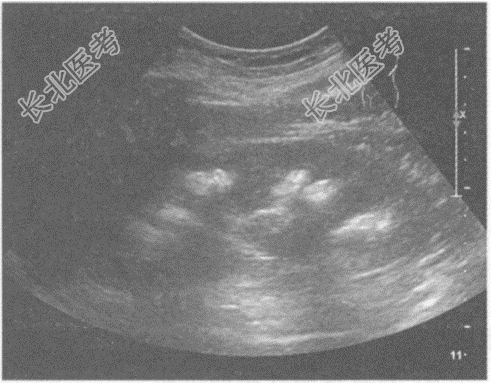

- 单项选择题临床资料:女, 25岁,因反复四肢麻痹10年, 腰部疼痛、肉眼血尿3月余入院。

化验检查:尿常规红细胞3+。

超声综合描述: 双肾形态、大小正常,沿肾锥体分布可见多个强回声光团, 后伴声影。

超声提示: A、双肾钙乳症

B、双肾海绵肾

C、双肾多发结石

D、双肾多发钙化

E、双肾错构瘤